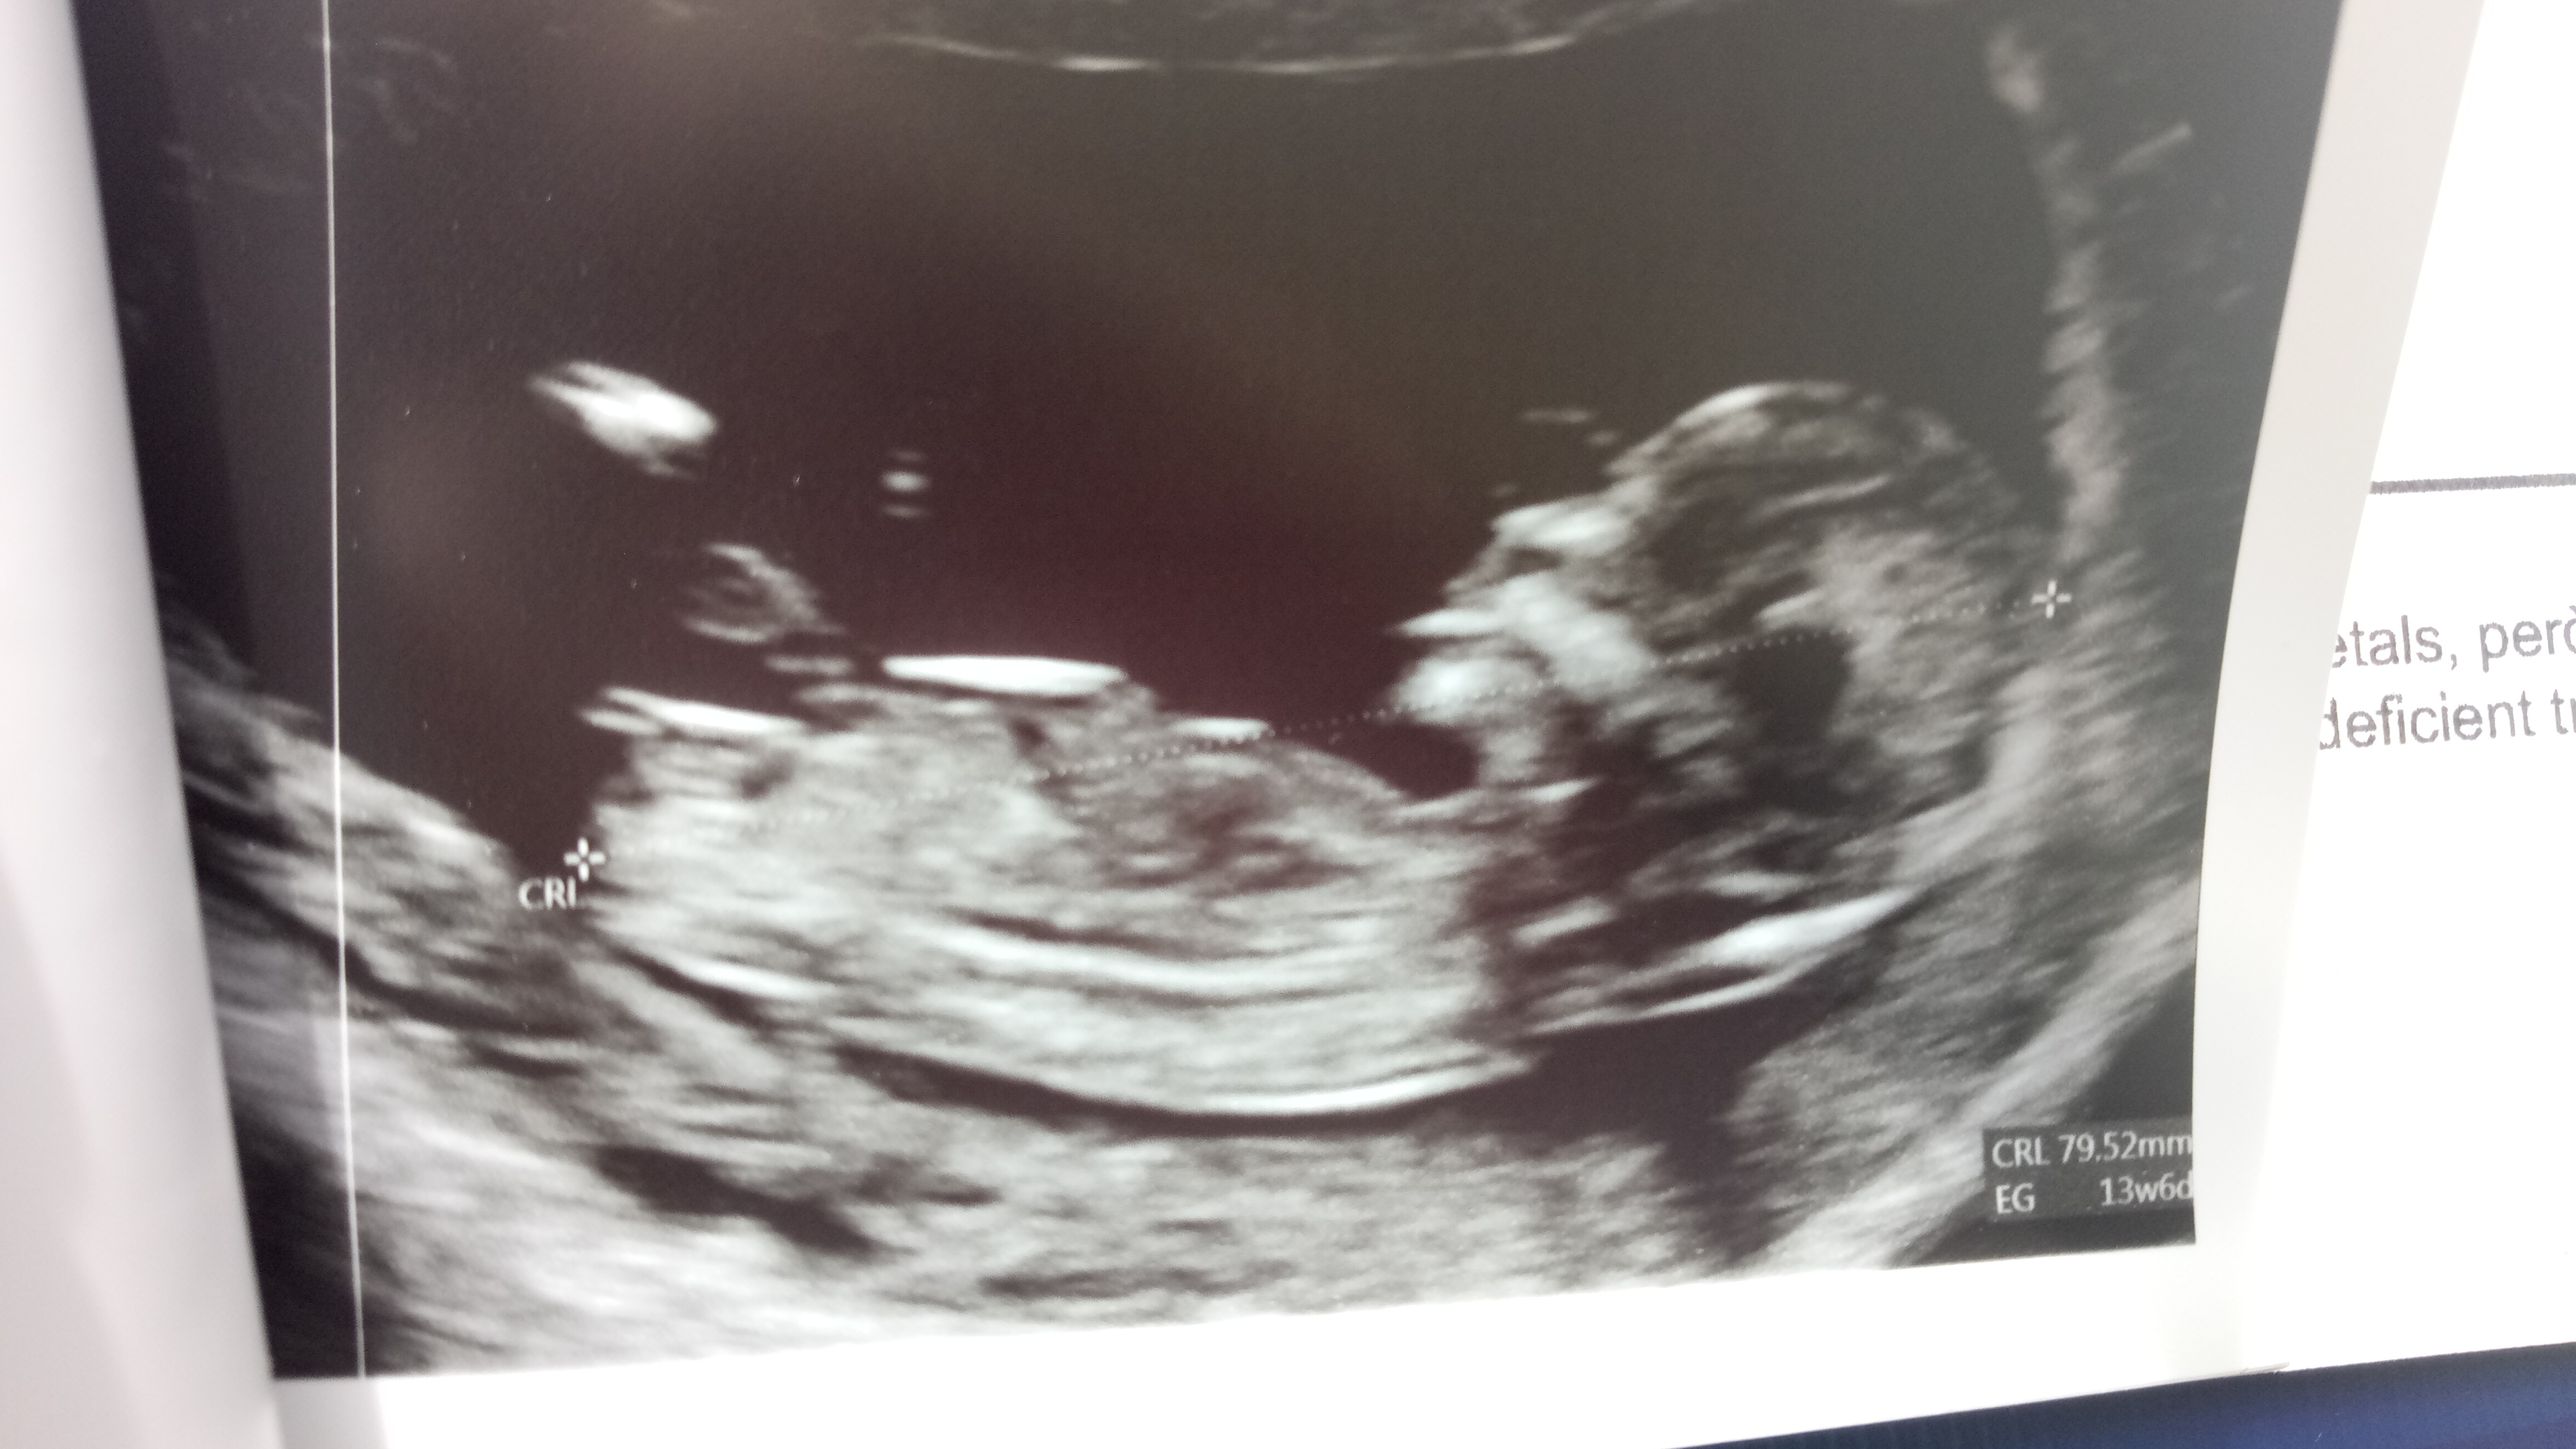

Witam mam pytanie jestem w 21 tygodniu ciąży. W 15 tygodniu dowiedziałam się ze będzie chłopak wczoraj na połówkowy lekarz powiedział ze chłopak pokazał mi niby siusiaka ale nie widziałam jąder czy może to jeszcze się zmienić i będzie dziewczynka ? Dołączam zdjęcie

• 91F95E4E-F923-4EE1-B654-476D712BA189.jpeg

91F95E4E-F923-4EE1-B654-476D712BA189.jpeg

34,7 KB · Wyświetleń: 625